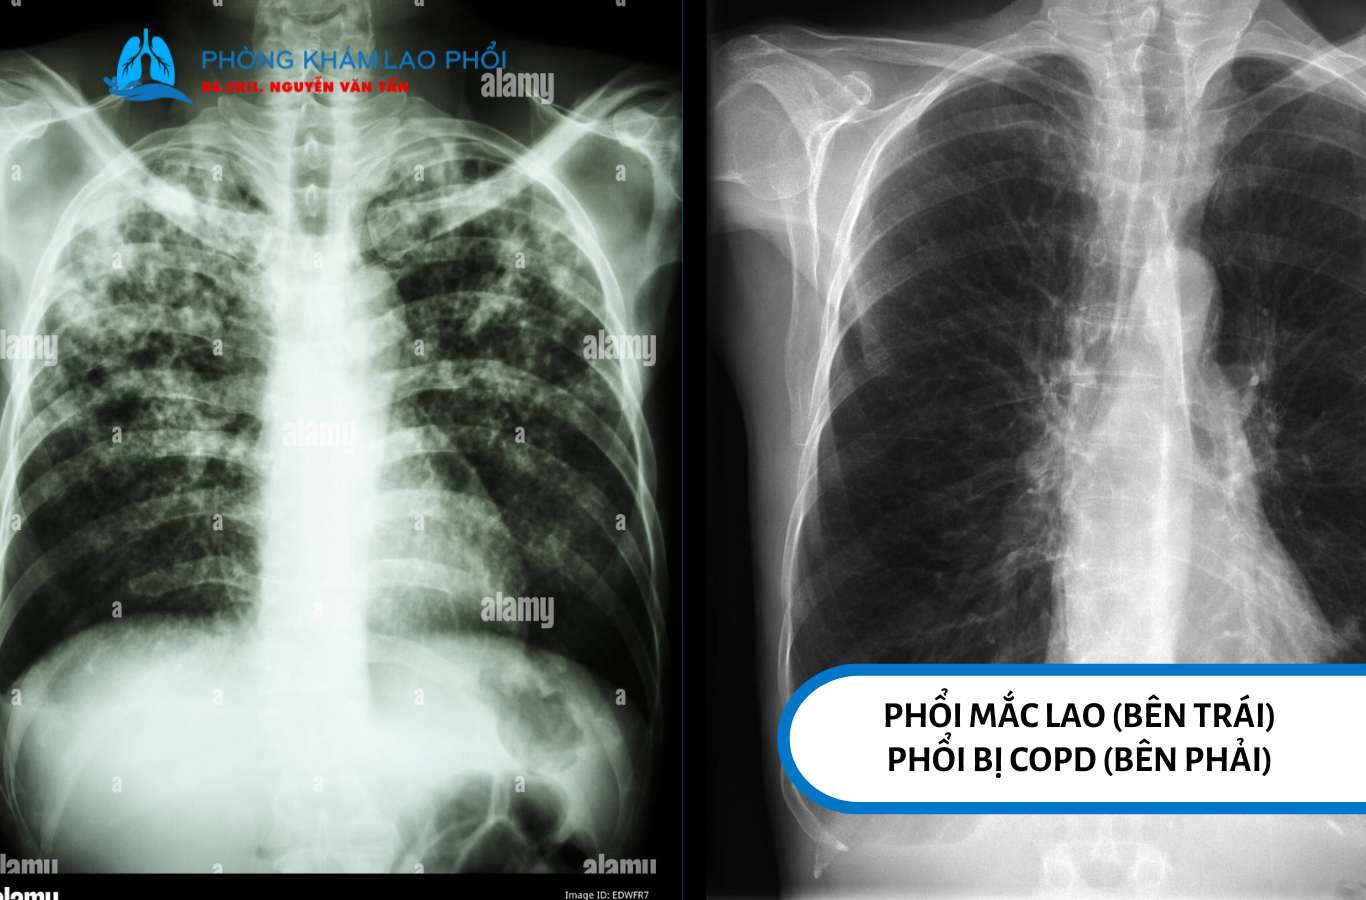

Tình trạng phổi khi mắc lao phổi và khi phổi bị tắc nghẽn mạn tính